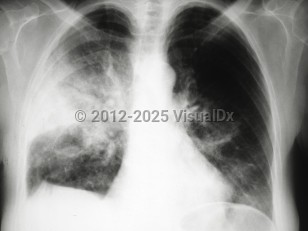

Pneumothorax

Spontaneous pneumothoraxSpontaneous pneumothorax